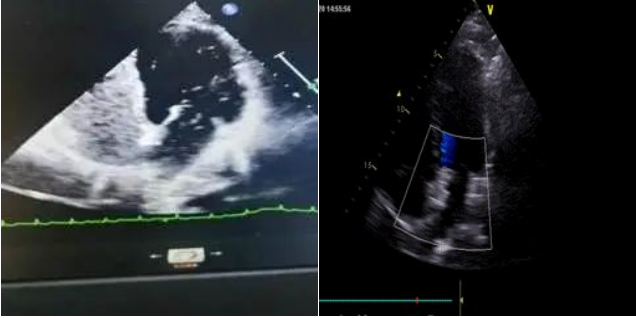

临床上对卵圆孔未闭的生理及病理意义的研究发现,卵圆孔未闭是很多不明原因卒中、偏头痛、矛盾性栓塞的罪魁祸首。除上述疾病本身的临床表现外,卵圆孔未闭无明显不适症状,查体亦无阳性表现。普通经胸超声的诊断价值有限,但右心超声造影+经食道超声可以明确诊断。对于有指征的患者,主要治疗手段为介入封堵治疗。

其中的典型病例是一位42岁的中年女性,她因“突发右侧肢体活动不利伴言语不利”入院,之前有偏头痛史,但没有动脉硬化高危因素。因发病年龄较轻,且无动脉硬化高危因素,入院后,我们仔细排查脑梗原因,头颅MRI提示多发脑白质缺血灶,头颈部血管CTA未见异常,考虑可能存在矛盾栓塞。进一步经右心造影检查证实,存在卵圆孔未闭、RLS分级III级,反常栓塞风险评分7分。评估后,我们对患者进行PFO介入封堵术,手术过程顺利,患者恢复良好。术后随访无不适症状,发作多年的偏头痛也意外改善。